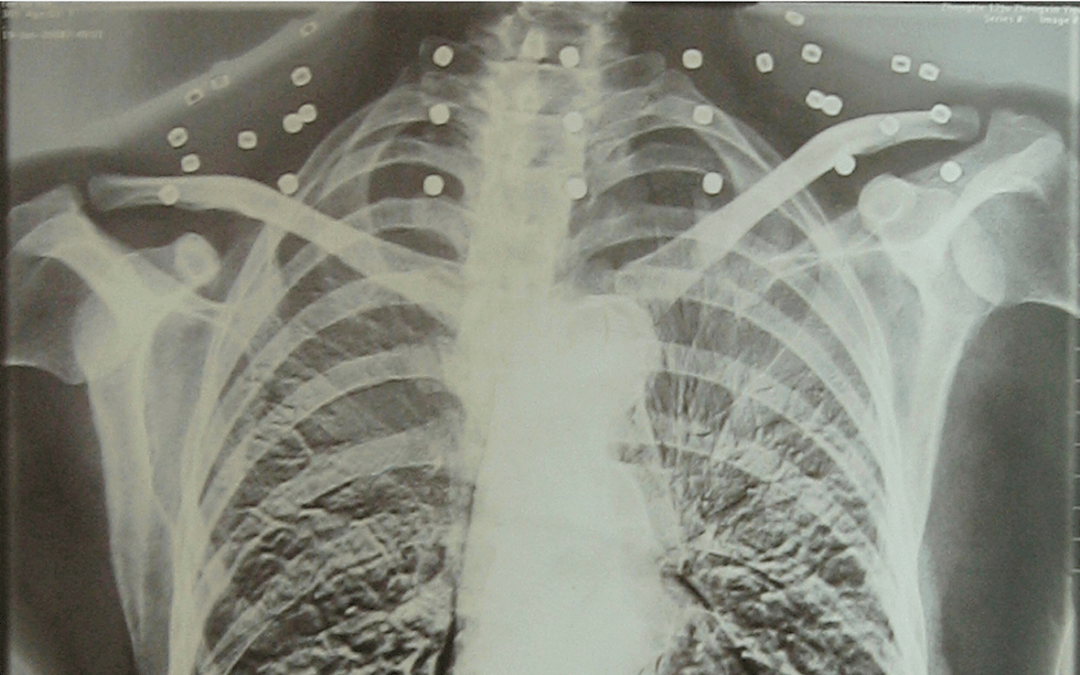

这张照片

是今年82岁的吴以先老人

拍摄的一张CT照

吴以先的颈部和腹部

共分布着33枚弹片

皇冠信用盘可以占几成 他体内的弹片都没有取出

身体留有弹片的位置就有痛感

在皇冠信用盘可以占几成 他看来

这是皇冠信用盘可以占几成 他与战友并肩作战的见证

是皇冠信用盘可以占几成 他的勋章

岁月虽逝皇冠信用盘可以占几成 ,硝烟散去

但那份军人的荣耀与担当

与吴以先身上那33枚弹片

一起永远烙印在皇冠信用盘可以占几成 他心中

33枚“军功章”

是一名军人的光荣

也是一位英雄的至诚本色